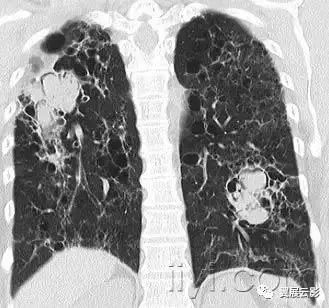

四十、曲菌球

病理:曲菌球是孤立的菌丝相互缠绕形成的肿块,常是曲菌类病原,黏液、纤维素、细胞碎片共同构成空洞成分,常发射跟你在纤维空洞的基础上(例如结核或者结缔组织病)

平片和CT:曲菌球可以随着体位的变化发生变化,部分病例可见空气新月征(图)CT上可以呈现海绵样影像和曲菌球内的钙化灶。同义词是真菌球。